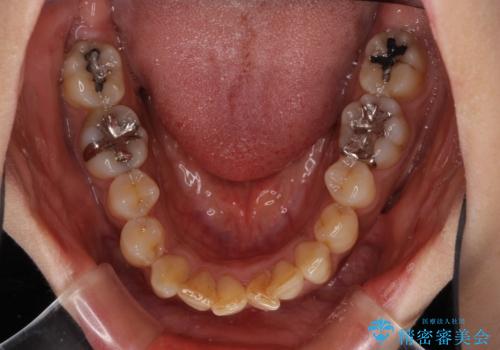

- 上下前歯のデコボコ改善をインビザラインにて行いたいとのことで来院された患者様です。

インビザラインをご希望のことで、IPR(歯と歯の間を削る)などによりスペースを獲得して、排列していくこととしました。

骨格的に上下顎が左右にずれていたため、正中位置は現状を維持したまま歯列不正を解消していくことになります。

なかなか装着時間が守れず、後戻りを繰り返しながら治療を進めたため、インビザライン治療期間期限ギリギリの5年弱の期間を要しました。